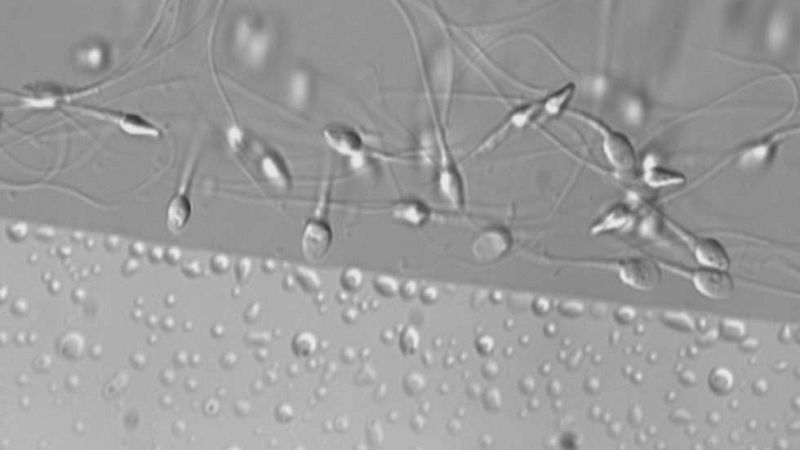

Aproximadamente tres de cada diez hombres en edad fértil tiene semen de mala calidad, inferior a los estándares marcados por la OMS. Son datos que se han presentado en un congreso sobre reproducción asistida que se celebra en Madrid. Factores ambientales, el estrés o una mala alimentación están detrás en la mayoría de los casos.

No era la primera vez que se intentaba pero sí la que ha dado resultado. Meses de estudio en un laboratorio chino para lograr no solo crear esperma a través de una célula embrionaria de ratón sino también fecundar con ello a varias hembras que dieron una camada de seis crías totalmente sanas. Las científicos chinas que han controlado todo el proceso in vitro, empezaron por extraer células germinales de los testículos del ratón y cultivarlas en un entorno parecido.

- Con los espermatozoides, han logrado obtener crías de roedor sanas y fértiles

- El descubrimiento puede servir para tratar la infertilidad masculina humana